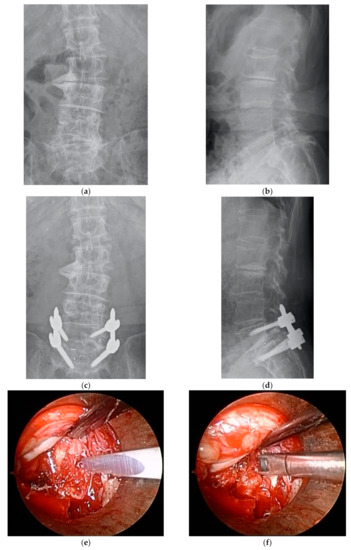

A total of 155 consecutive patients who met the aforementioned inclusion criteria were registered for the study. Six of these patients lacked complete preoperative data; therefore, 149 patients were eligible for analysis. Of these patients, 72 underwent ME-PLIF (ME group), and 77 underwent open PLIF (open group); the specific procedure was determined at each hospital. Two facilities performed ME-PLIF on all patients with the single-level disease, while three facilities performed open PLIF on all patients; at a sixth facility, both procedures were performed. ME-PLIF procedures were performed in accordance with previously reported guidelines [12]. First, a 20 mm incision was made into the skin 15 mm symptomatic outside from the midline on the level of the intervertebral disc. Subsequently, using fluoroscopic guidance, a METRx (18 mm, Medtronic Sofamor Danek., Dublin, Ireland) or ESD II tubular retractor (20 mm, Japan Medical Dynamic Marketing, Inc., Tokyo, Japan) was placed at a site overlying the disk space. All procedures leading to interbody fusion, including decompression, removal of an intervertebral disc, grafting of autologous bone and cage insertion, were performed within the microendoscopic field connected to the tubular retractor. Either a polyetheretherketone (PEEK) or titanium interbody cage filled with autologous bone was inserted. After the microendoscopic procedure, pedicle screws were inserted percutaneously under fluoroscopic guidance. We indicated the perioperative and postoperative radiographs, intraoperative microendoscopic surgical field and postoperative wound in patients who underwent ME-PLIF (Figure 1). The traditional open PLIF was performed via a posterior midline incision. After unilateral or bilateral decompression of the spinal canal, grafting of autologous bone and cage insertion was performed at one or both sides. Pedicle screws were inserted from the same surgical field.

Figure 1.

(a) Preoperative anterior-posterior (AP) radiograph. (b) Preoperative lateral radiograph. (c) Postoperative AP radiograph. (d) Postoperative lateral radiograph. (e) Removal of the intervertebral disc, intraoperative microendoscopic surgical field. (f) Curettement of the intervertebral disc, intraoperative microendoscopic surgical field. (g) Cage insertion, intraoperative microendoscopic surgical field. (h) Postoperative wound.